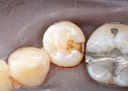

Mark Chun #13,14,15 prep